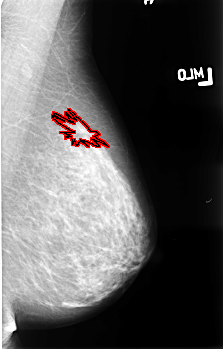

B_3477_1.LEFT_MLO

FILE: B_3477_1.LEFT_MLO.OVERLAY

TOTAL_ABNORMALITIES 1

ABNORMALITY 1

LESION_TYPE MASS SHAPE ARCHITECTURAL_DISTORTION MARGINS ILL_DEFINED-SPICULATED

ASSESSMENT 4

SUBTLETY 3

PATHOLOGY MALIGNANT

TOTAL_OUTLINES 1

BOUNDARY